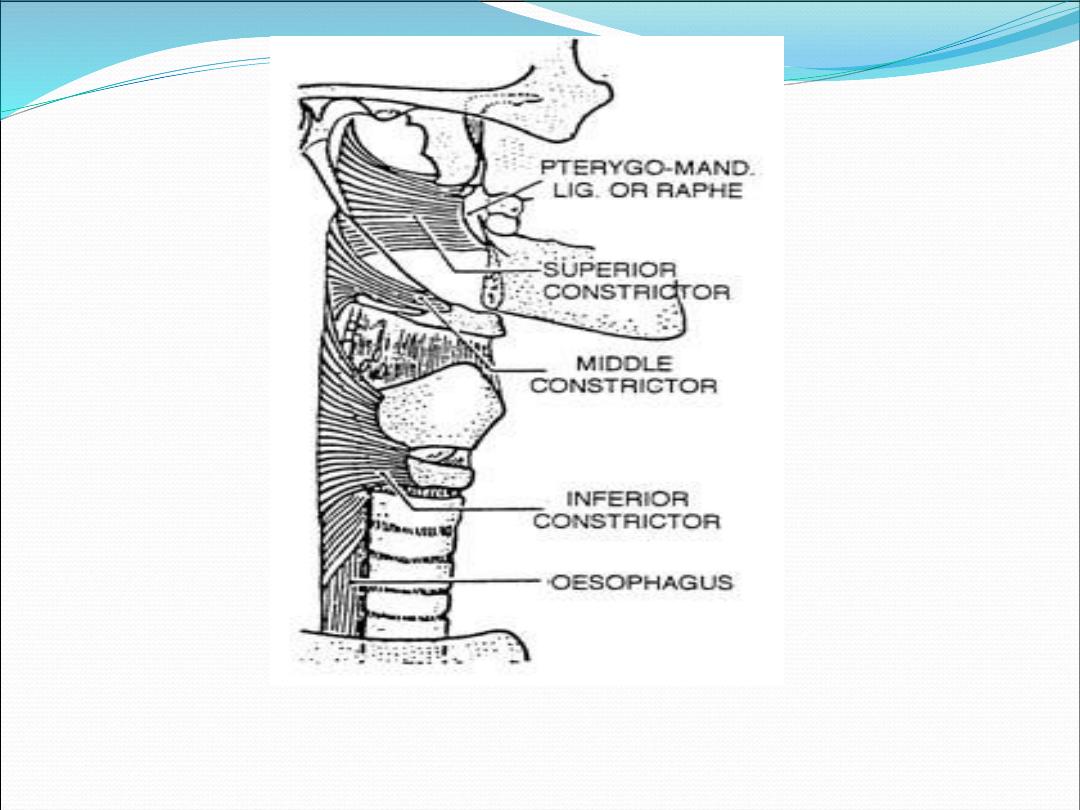

layers

Mucosa: non-keratinized stratified squamus

epithelium & ciliated columnar epithelium

Pharyngobasilar fascia: fibrous layer

Muscles : longitudinal and circular

Buccopharyngeal fascia: loose areolar tissue that

separate pharynx from prevertebral fascia

Inner layer

Salpingopharyngeus

Stylopharyngeus

Stylohyoid

Palatopharyngeus (posterior pillar)

Outer layer (constrictors)

Superior constrictor

Middle constrictor

Inferior constrictor